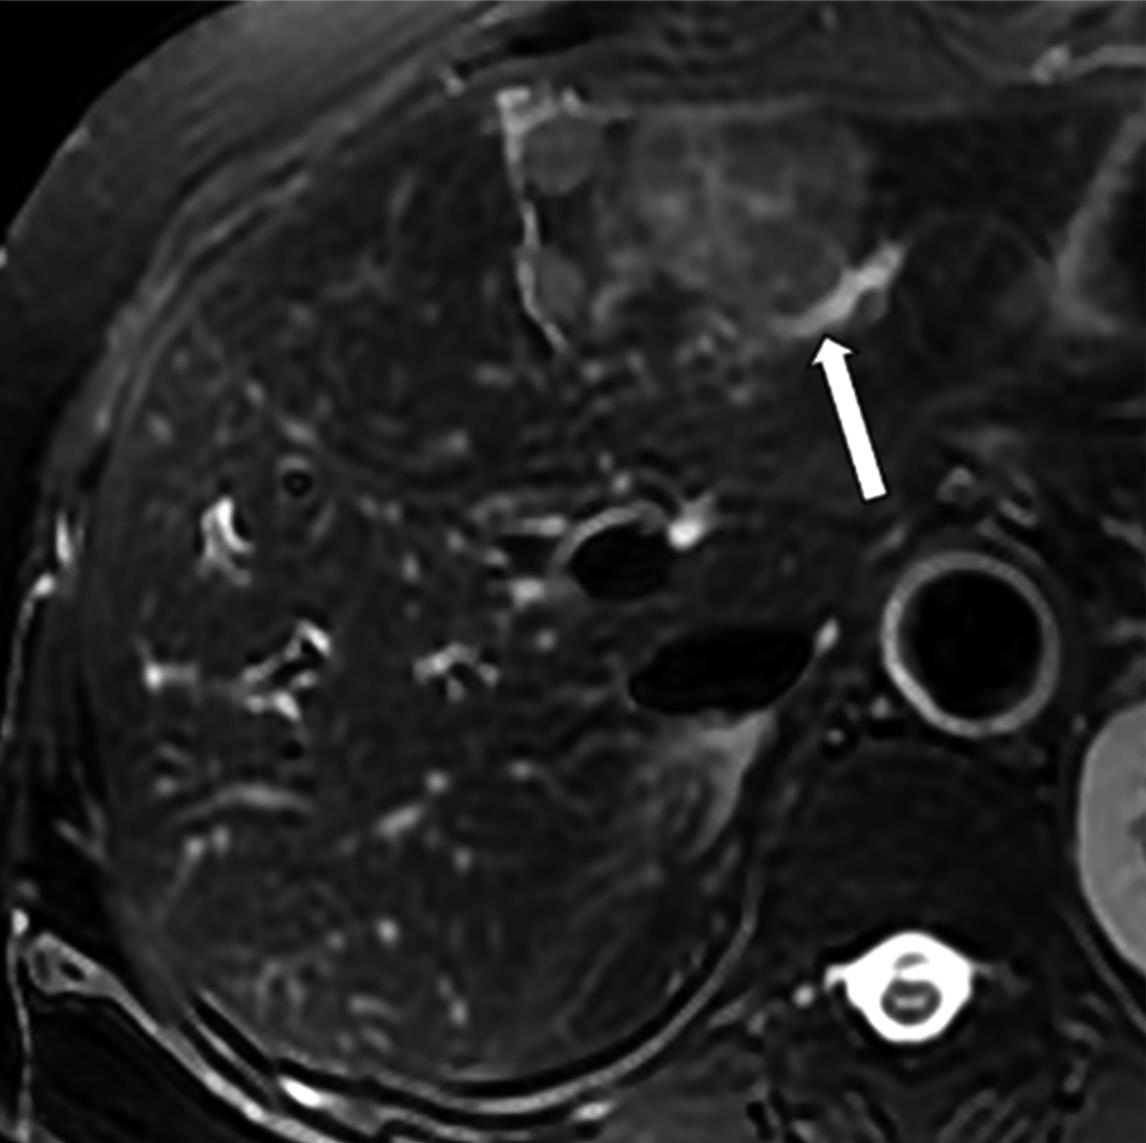

• MRI瘤周特征在预测结直肠癌肝转移非解剖性肝切除术预后的价值

摘要:目的 研究结直肠肝转移(colorectal liver metastases,CRLM)瘤周影像特征在非解剖切除(non-anatomic resection,NAR)后CRLM患者中长期预后的价值。方法 回顾性纳入术前行腹部钆塞酸二钠增强磁共振成像(magnetic resonance imaging,MRI)和NAR术后的CRLM患者。影像特征评估动脉期瘤周高强化、肝胆期(hepatobiliary phase,HBP)瘤周低摄取和瘤周胆管扩张。应用Kaplan-Meier法计算生存率,并采用Cox比例风险回归模型进行单因素和多因素分析以确定无肝内复发生存期(liver recurrence-free survival,LRFS)、无复发生存期(recurrence-free survival,RFS)和总生存期(overall survival,OS)的独立预测因素。结果 本研究共纳入36例患者,58个CRLM病灶。存在和不存在动脉期瘤周高强化的患者3年LRFS和RFS率有统计学差异(LRFS:14.3% vs. 43.9%,P=0.005;RFS:14.3% vs. 40.3%,P=0.006)。动脉期瘤周高强化与较差的LRFS(P=0.002,HR=5.541,95%CI=1.853~15.975)和较差的RFS(P=0.002,HR=5.392,95%CI=1.887~15.412)独立相关。胆管扩张和HBP瘤周低摄取均不为LRFS、RFS和OS的独立预测因素。结论 动脉期瘤周高强化是接受NAR的CRLM患者LRFS和RFS预后因子。